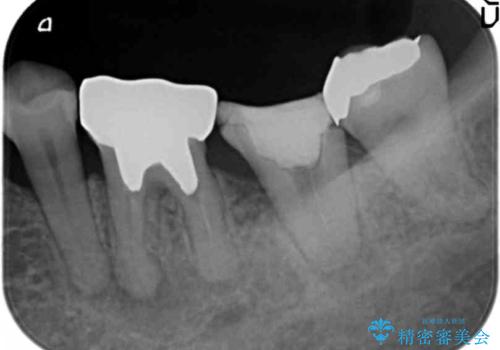

移植後、生着を待って根管治療及び補綴修復を行いました。

※術前にレントゲン・CTを撮影し、抜去する歯と親知らずの根の長さ・幅径・形態を確認し、移植の可否を判断してから手術を行っております。

左下の奥歯(左下7)は破折しており保存不可能な状態でした。

ご希望により、隣の親知らず(左下8)を移植しました。